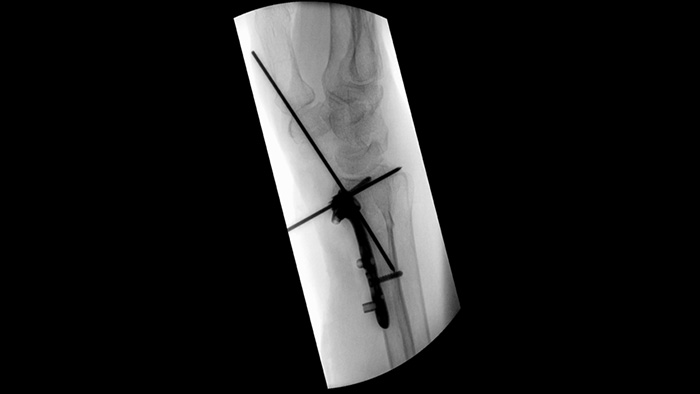

When setting pedicle screws for a spinal fusion or fracture repair, reducing technical distractions and discussions can help surgical teams remain focused on the patient. With Unify workflow’s navigation aids, surgical teams experienced smoother interactions and less miscommunication in a usability study.1

Simplify workflow for challenging orthopedic cases requiring frequent re-positioning of the mobile C-arm. With Position Memory,2 participants in a usability study1 achieved 94% first-time-right repositioning and experienced less frustration during (re)positioning tasks.